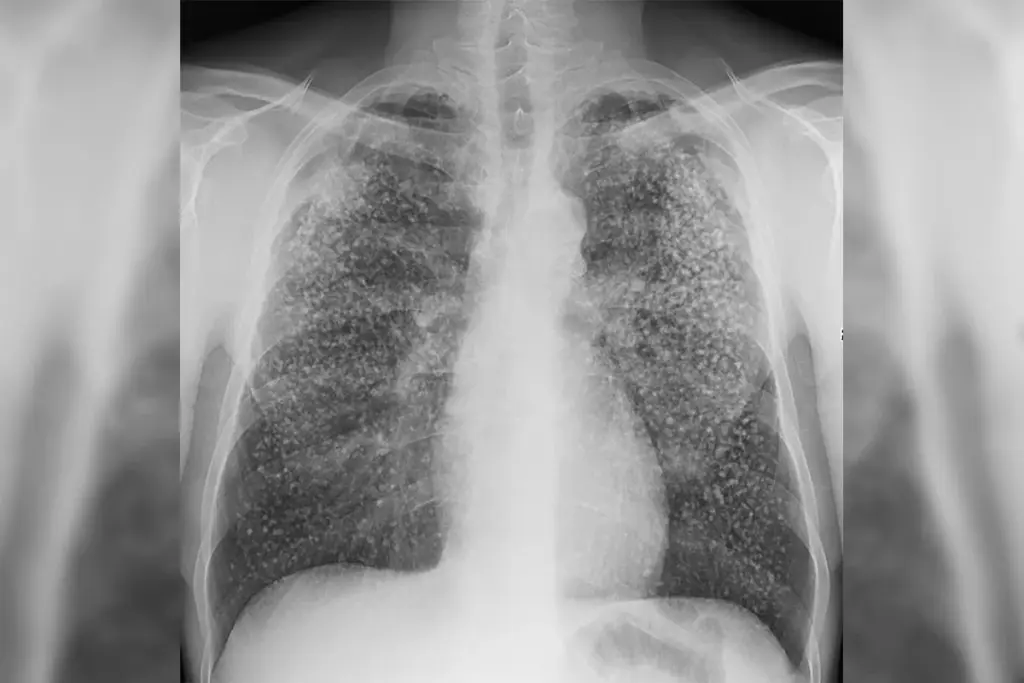

• Pulmonary Tuberculosis: This form accounts for the majority of active cases and is the primary driver of transmission. It involves the lung parenchyma and potentially the tracheobronchial tree. The disease can be further sub-classified based on the radiological presentation, such as cavitary disease (where large holes form in the lung tissue) or miliary tuberculosis (where the bacteria disseminate like millet seeds throughout the lung fields).